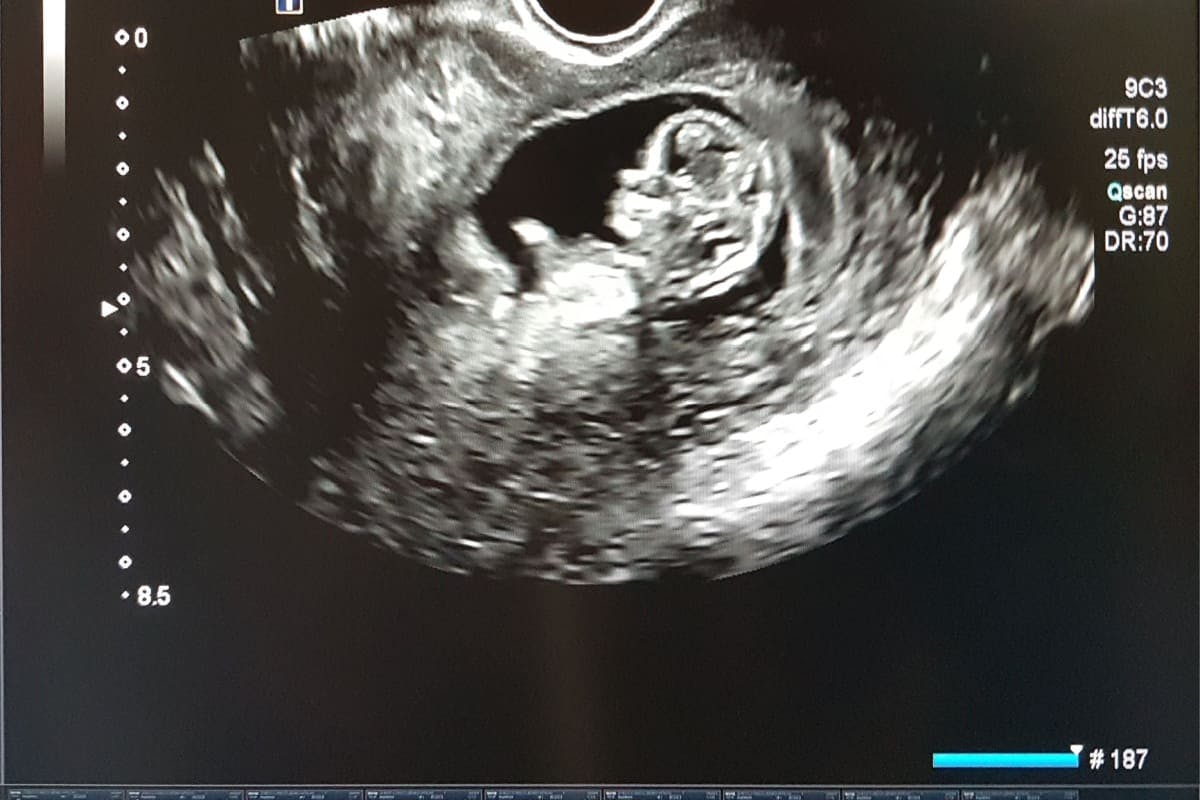

Morfologia fetală din primul trimestru este o investigație medicală importantă, care ajută la evaluarea dezvoltării bebelușului și la depistarea unor posibile anomalii. Realizată între săptămânile 11 și 14 de sarcină, aceasta permite medicilor să monitorizeze creșterea fătului, să măsoare anumite zone ale corpului și să observe eventualele semne ale unor afecțiuni genetice sau structurale. Această ecografie este un pas esențial pentru orice femeie însărcinată, oferindu-i informații valoroase despre evoluția sarcinii și despre starea de sănătate a fătului. În continuare, vei descoperi ce anomalii pot fi identificate la morfologia fetală din primul trimestru și cum se desfășoară această investigație.

Dacă te întrebi ce înseamnă morfologie fetală, ei bine, ecografia de morfologie fetală de trimestrul I reprezintă, alături de analizele specifice sarcinii, o investigaţie extrem de importantă. Rolul acestui screening este acela de a depista eventuale anomalii cromoziale şi malformaţii fetale. Ecografia se face, de obicei, în săptămânile 11-13+6 săptămâni de sarcină și analizează uterul mamei și dezvoltarea fătului [1].

În timpul screening-ului de morfologie fetală de trimestrul I, medicul specialist evaluează riscul de apariţie a sindromului Down şi a trisomiilor 13 şi 18. Testul poate depista precoce anomalii fetale majore sau malformaţii grave. Ecografic, se va măsura lungimea craniocaudală, translucența nucală, ductul venos, osul nazal, fluxul prin valva tricuspidă şi frecvenţa cardiacă. Află mai multe și despre morfologia fetală de trimestrul II și despre importanța acesteia!

Morfologia de trimestrul I este o investigație medicală importantă, care se efectuează în perioada timpurie a sarcinii, de obicei între săptămânile 11 și 14 de sarcină. Această ecografie detaliată are scopul de a evalua dezvoltarea embrionului sau a fătului și de a detecta eventuale anomalii sau riscuri asociate sarcinii [2].

În cadrul morfologiei de trimestrul I, ecografia este principalul instrument folosit pentru evaluarea fătului. În această perioadă, ecografia poate fi realizată pe cale abdominală sau pe cale transvaginală, în funcție de poziția fătului și de accesibilitatea zonei. Ecograful va emite unde sonore care sunt reflectate de structurile interne ale corpului, iar imaginea va fi vizualizată pe un ecran. Aceasta permite medicului să examineze detaliile anatomice ale fătului și să măsoare diferite zone esențiale ale acestuia [5].